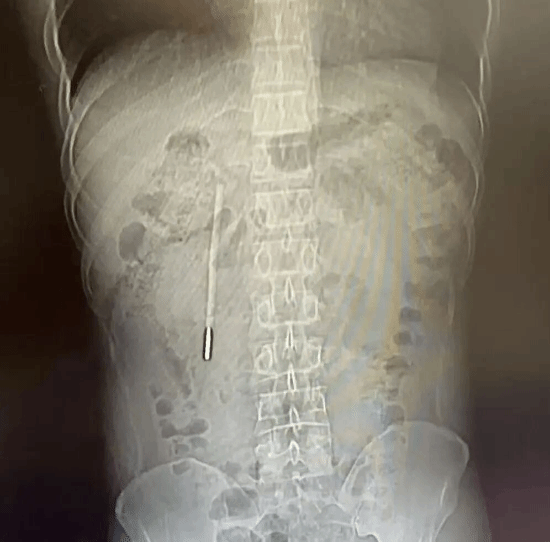

结果在CT检查中发现其十二指肠内竟藏有一根清晰的异物,经追溯病史这竟然是他20年前、年仅12岁时不慎误吞的一根水银体温计!

检查发现,这根体温计前端已紧贴肠壁,随时可能引发肠穿孔、消化道大出血等致命风险,所幸医护团队通过内镜微创技术,仅用20分钟就将其完整取出。

让人称奇的是,在体内待了20年的体温计除刻度消失外,外观基本完好,未发生破碎,水银也未流出,患者术后顺利恢复。